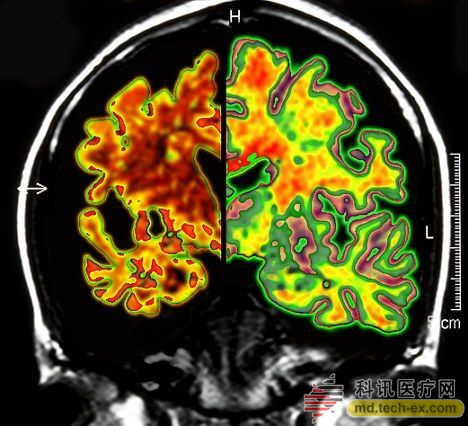

在手術(shù)中,所有病患的腦部將被植入電極,這些電極與一個(gè)類似起搏器的裝置相連接,能夠每秒鐘發(fā)出130次電脈沖。羅森博格表示,病人并不會(huì)感受到電脈沖的存在。 研究人員表示,所有接受臨床試驗(yàn)的病人同時(shí)都會(huì)被植入這個(gè)“起搏器”裝置。其中,一半病人的“起搏器”將于手術(shù)后兩周開啟,而另一半病人的要在手術(shù)后一年才會(huì)開啟。目前,參加臨床試驗(yàn)的病人和醫(yī)生并不知道分組情況。 其實(shí)早在2010年,加拿大就已經(jīng)對(duì)這種大腦“起搏器”展開臨床試驗(yàn)。當(dāng)時(shí),有6名輕微老年癡呆癥患者參加。當(dāng)時(shí)的試驗(yàn)結(jié)果顯示,在13個(gè)月的觀察期中,這些病患的葡糖糖代謝速度持續(xù)上升,這也就說明他們的大腦神經(jīng)元正在工作。而在同時(shí)期內(nèi),大部分老年癡呆癥患者的葡萄糖代謝水平則是在不斷下降。